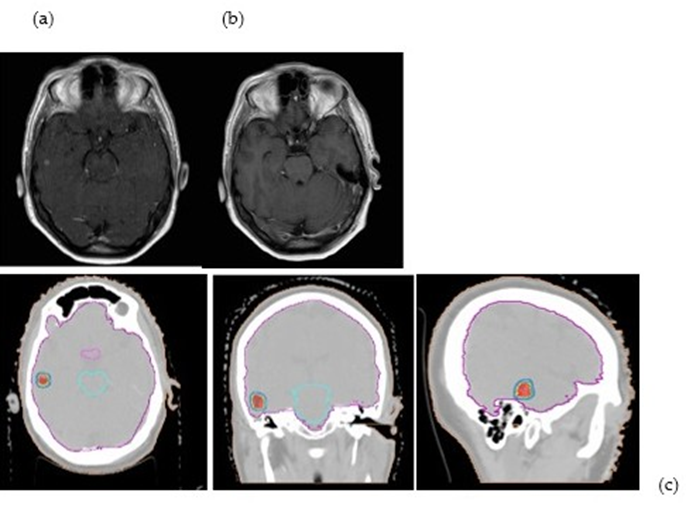

Numerous Osimertinib resistance pathways have been found, including histologic change, secondary EGFR mutations, and MET proto-oncogene amplification. Patients with BMs upon diagnosis still constitute a challenging-to-treat minority in this situation, which could have an impact on quality of life in the event of local development and result in poorer outcomes [32]. (Figure 1)

Figure 1: The figure shows an SRS (21 Gy/1fx) of a patient with EGFR t790MUT with a single brain metastasis on pre-RT MRI a) in complete response 45 days post-treatment b) The treatment plan c) shows the dose distribution (95%-130%)